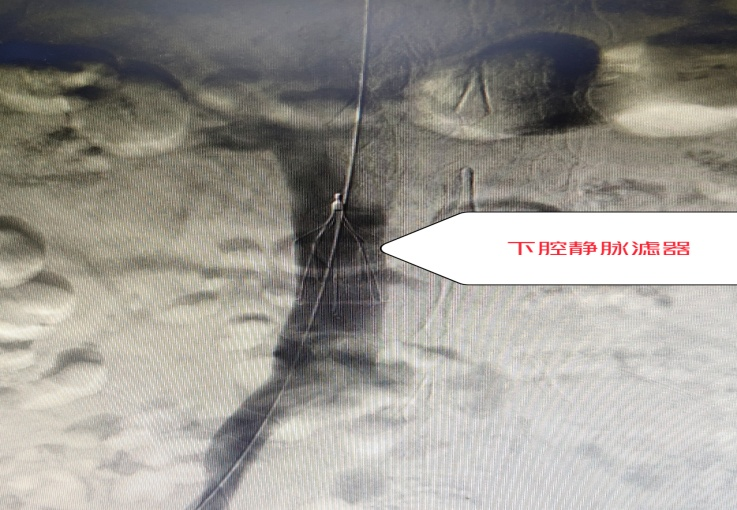

下肢静脉滤器

考虑到老刘左下肢深静脉血栓持续形成且仍有脱落加重肺栓塞的风险,胡博士首先穿刺右侧股静脉放置下腔静脉滤器,拦截血栓。再经过穿刺的小口用导丝带导管进入肺动脉进行溶栓治疗。